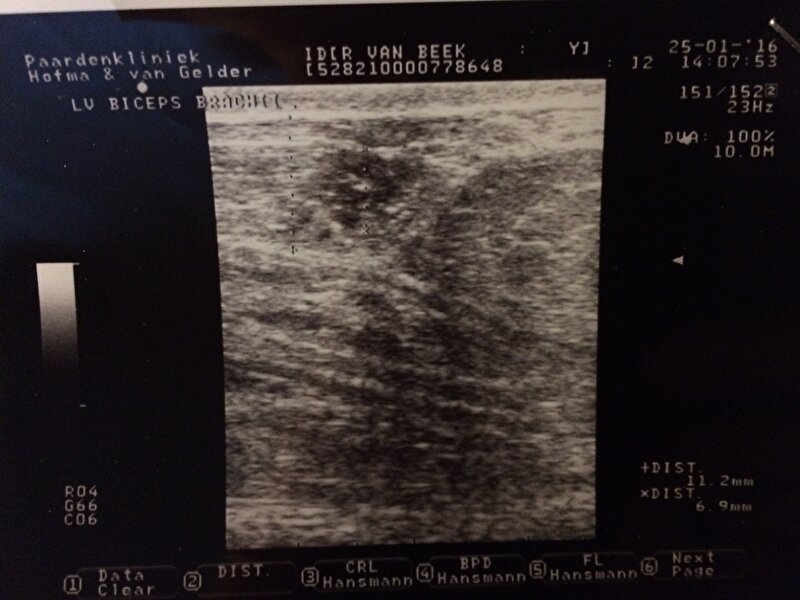

Afbeelding

Op deze eerste foto zie je de ontsteking. Normaal bij een ontsteking is het gewoon rond met alleen maar vocht. Omdat ze waarschijnlijk al een hele tijd met deze ontsteking rond loopt is het bij haar een beetje gespikkeld.